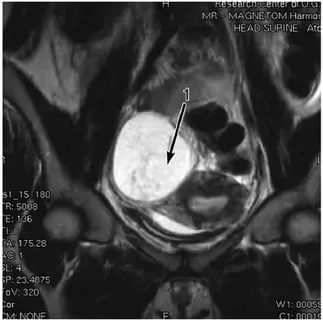

Диагностика обычно включает гинекологический осмотр, ультразвуковое исследование и, в некоторых случаях, магнитно-резонансную томографию (МРТ). Эти методы помогают визуализировать кисту и оценить её размер и расположение.